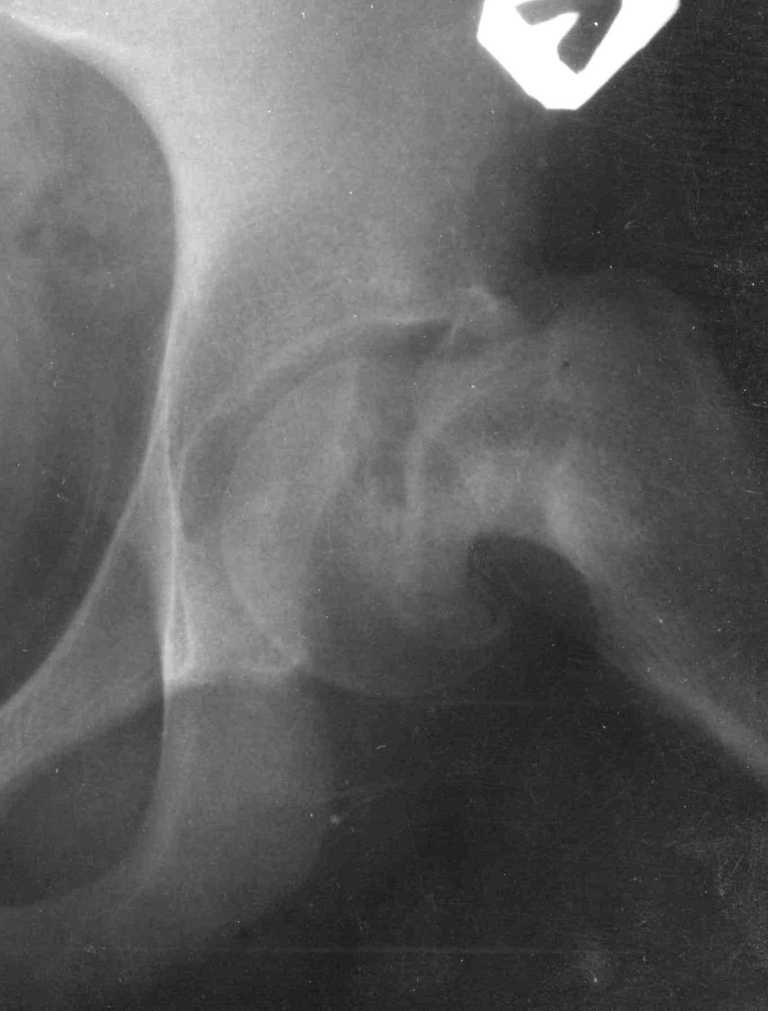

Ребёнок 14 лет. Весом под центнер. Имеющаяся рентгенологическая деформация деформация - на момент поступления.

Госпитализирован ребёнок 14 лет. Мальчик, мягко говоря, крупный, гиперстенического типа сложения, ближе к десантнику. Весит 95 кг. Ожирение 2-й степени. Со слов больного - испытывает дискомфорт в области тазобедренного сустава в течение 3-х месяцев. На рентгенограммах - положение дел на момент поступления - конец мая. Укорочение конечности на 1,5 см. Ограничение внутренней ротации. Ходит, едва заметно прихрамывая на больную ногу. Эндокринологический статус находится в стадии обследования. Выполнена рентгенография в стандартных укладках, спиральная КТГ. Ясное дело, головка бедра <ушла> вниз и кзади. Пытающаяся <поймать> её шейка варизировалась и исполнила ретроверсию, создав изгиб во фронтальной плоскости. На рентгеноскопии - подвижность головки не определяется. Мальчик имеет далеко идущие планы на обустройство собственной жизни и образование. Крайне негативно относится к длительной иммобилизации и консервативному лечению. Загодя не согласен со снижением качества жизни в процессе лечения. Мнения коллег относительно дальнейшего лечения разделились. Успешность репозиции головки под наркозом - сомнительная в связи с имеющейся деформацией шейки бедра. Одни склоняются к тактике невмешательства - разгрузка больной конечности, ФЗТ , массаж, и т.д. Предлагают ждать завершения процесса <сползания> головки в условиях полной разгрузки, <тянуть> сустав до эндопротезирования как можно дольше. Другая группа коллег предлагает немедленную стабилизацию головки, что, кажется, правильно. Принимая во внимание анатомическое соотношение головки и шейки бедра, способ остеосинтеза так же вызвал массу споров, не приведших к единому и окончательному мнению. Пока дискуссия остановилась на стабилизации спицами Бека под контролем ЭОП, возможно с применением электродов для проведения электростимуляции слабыми импульсными токами. Техника проведения спиц, однозначно, будет сопряжена с техническими трудностями, обусловленными имеющейся деформацией шейки. Как бы Вы поступили, коллеги, в данной ситуации? Заранее спасибо. И прошу прощения за качество спимков. Буду отправлять их по очереди.